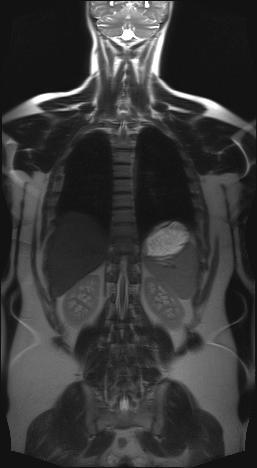

Röntgenbild der gleichen Person fast fehlende Bandscheibe Entzündung ist im Röntgenbild nicht zu erkennen. Es handelt sich um eine Schnittbild im coronaren Strahlengang parallel zur Stirn Der weisse Fleck ist ein Anschnitt der Aorta die dort einen Bogen macht. Bei der Diagnose von Intervertebralhernie und Instabilität der Wirbelsäule in den Bereichen der Übergangswirbel ist es sehr bezeichnend MRI mit Vertikalisierung durchzuführen.

Unschlagbar Die Ganzkorper Mrt Bei Knochenmetastasen Healthcare In Europe Com